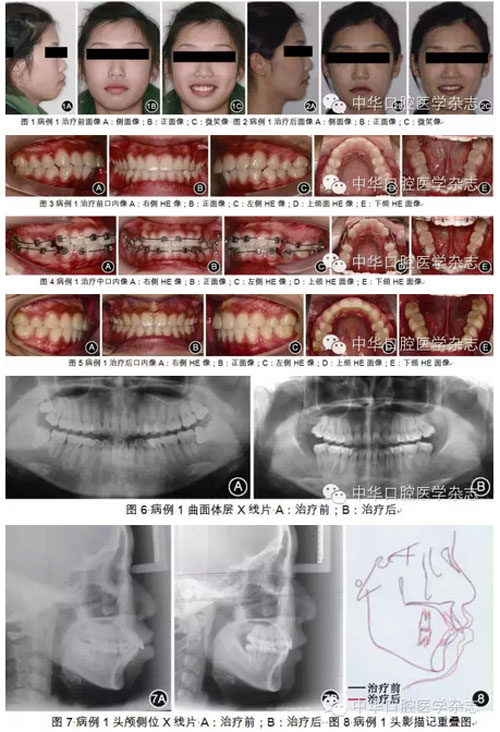

長、露齦笑、唇肌閉合不良等后果,使面形無法有效改善。因此,對于前突的Ⅱ類錯(cuò)HE患者,為了達(dá)到控制上頜前牙-牙槽骨(或上頜骨)并使下頜向前向上變化的目的,必須:①先使用向上向后的矯治力遠(yuǎn)中直立下頜磨牙,將下頜前牙內(nèi)收直立于基骨上,同時(shí)維持或適度后傾上頜磨牙,使上頜前牙向上向后移動(dòng);②用使下頜向前向上的矯治力使下頜產(chǎn)生相應(yīng)反應(yīng)。垂直向控制必須貫穿整個(gè)治療過程,即必須控制磨牙的垂直位置,同時(shí)控制下頜平面、腭平面和HE平面。